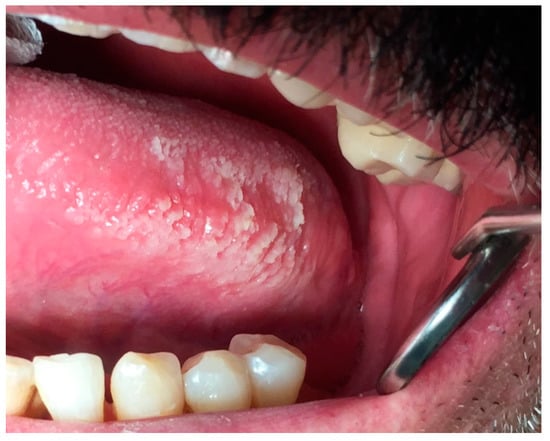

6.3. Oral Hairy Leukoplakia

| OHL | NA | M | borders of the tongue unilaterally or bilaterally | from slight, white vertical bands to thickened, furrowed areas with a shaggy surface | systemic anti-herpes virus drugs, topical retinoids or podophyllum resin, combination therapy with acyclovir cream and podophyllumresin, gentian violet, surgical excision or cryotherapy | no potential for malignant transformation |